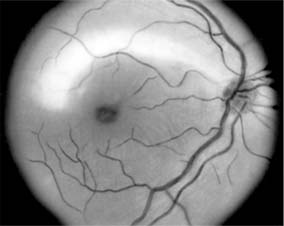

Figure 14-17

Figure 14-17: Large patch of myelinated nerve fibers originating from superior edge of disk. Another smaller patch is present near the inferior nasal border of the disk. (Right eye.)